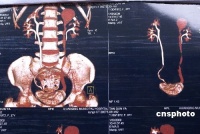

肾移植造影